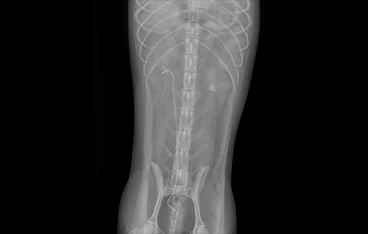

• 횡격막탈장 수술 전

횡격막탈장 수술 후